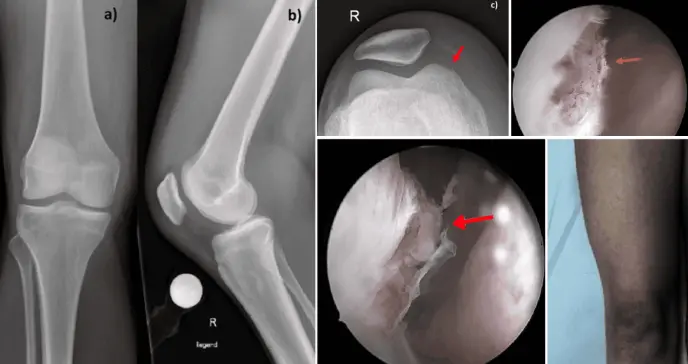

Además, los cultivos revelaron la presencia de una bacteria llamada Enterococcus faecium. Los análisis de sangre confirmaron que su cuerpo estaba luchando contra una infección importante, con glóbulos blancos elevados y marcadores de inflamación muy altos. Las radiografías descartaron fracturas pero mostraron un importante acúmulo de líquido dentro de la articulación.

Radiografías de la rodilla derecha lesionada, tomadas en la primera visita a urgencias para observar el derrame articular y descartar una fractura. a) Muestra la vista anteroposterior; b) la vista lateral; y c) la vista tangencial de la rótula. En la imagen c , se observa la irregularidad de la cortical en el cóndilo femoral medial (flecha roja).